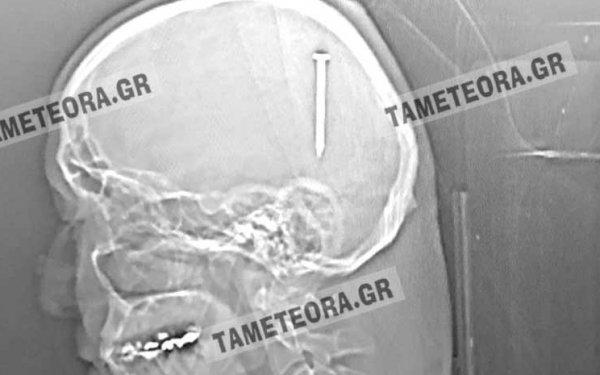

Σπάνιο περιστατικό – θαύμα για Καλαμπακιώτη, που του μπήκε καρφί στο κεφάλι!

Ένα πραγματικό θαύμα έζησε πρόσφατα ένας Καλαμπακιώτης.